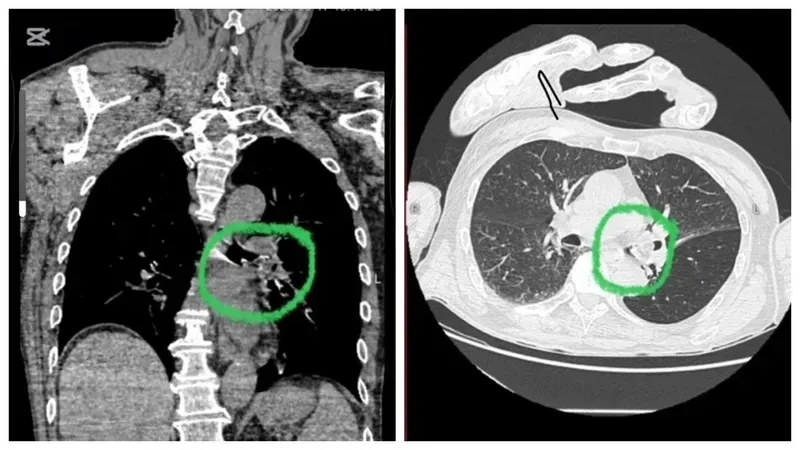

"53 жасар әйел қан қысымын төмендету үшін интернеттегі кеңестерге сүйеніп, "куркума" мен "алма сірке суын" ішкен. Нәтижесінде, анафилактикалық шокқа түсіп, өте ауыр жағдайда ауруханаға жеткізілді. Диагнозы: Лайелла синдромы – аллергиялық буллёзды дерматиттің ең ауыр түрі. Науқас 2 күн бойы өте ауыр жағдайда жатты, бүгін ғана есін жинады. Құрметті достар, халықтық емдеу әдістері кейде тиімсіз болып, денсаулығыңызға үлкен зиян келтіруі мүмкін. Сақ болыңыздар…", - деп жазды бас дәрігер.